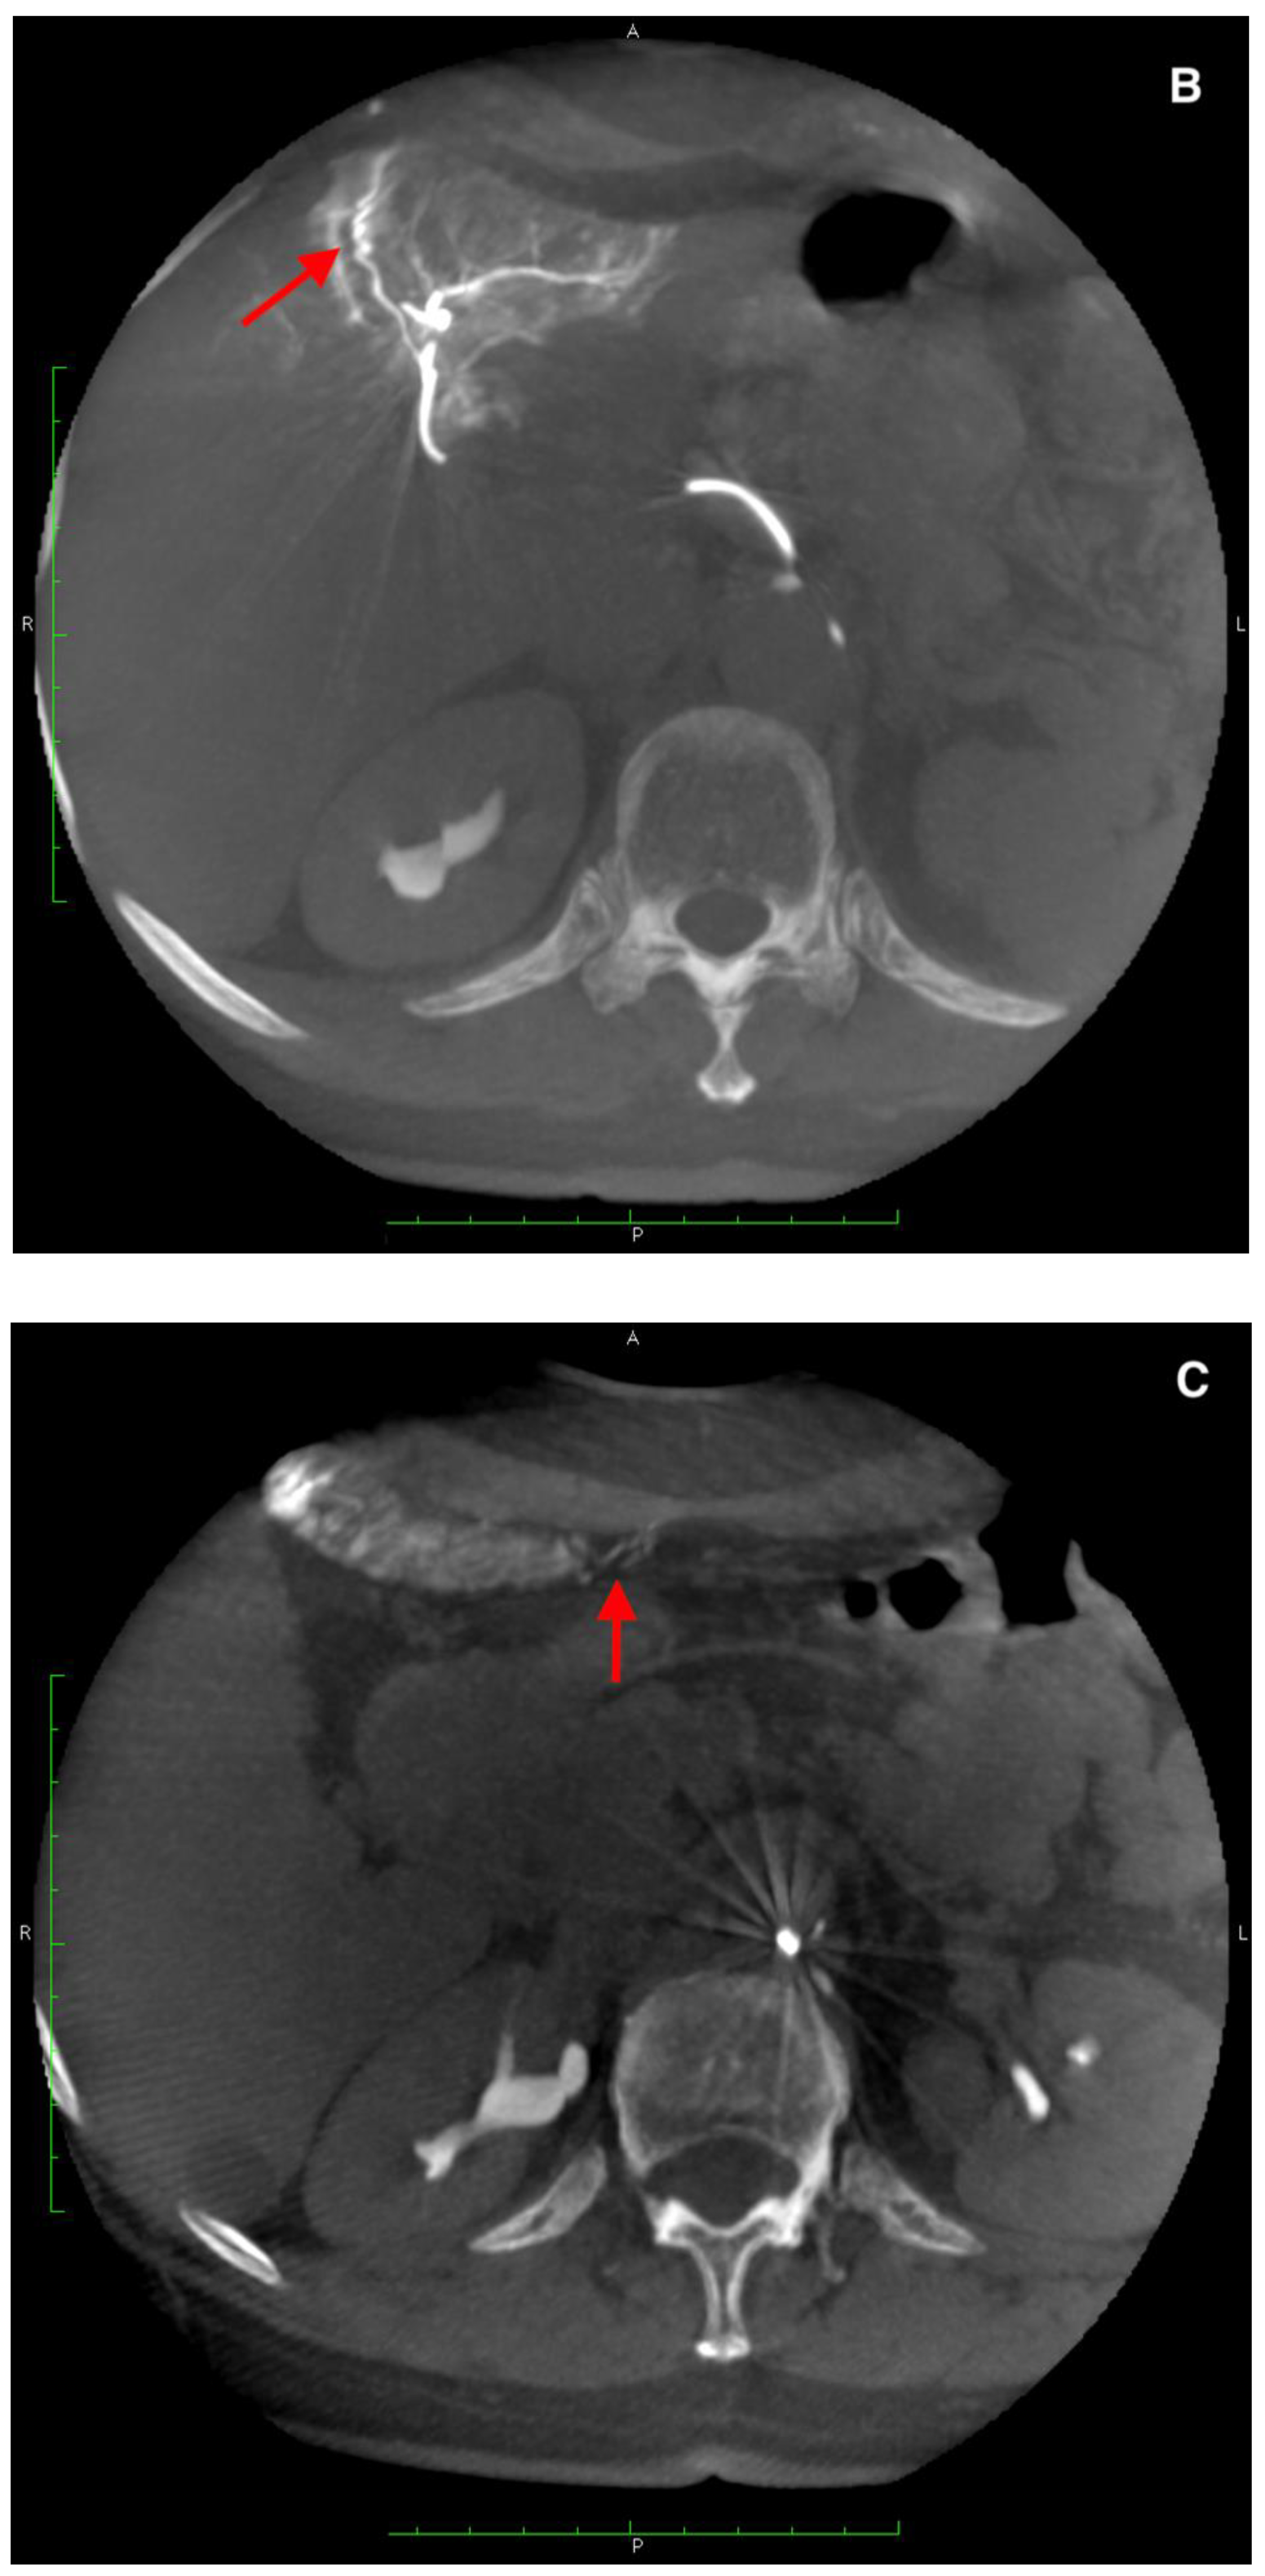

There were two leaks into the gallbladder wall after SIRT administration. Both patients had no signs of cholecystitis or a bilirubin level elevation (Figure 6 and Figure 7). No leaks were noticed in the group of five requalified patients.

Figure 6.

(A) Angiogram of the left hepatic artery showing falciform artery travelling medially beyond the margin of the liver. (B) Its presence was confirmed on Dyna-CT and showed contrast enhancement of the abdominal wall (arrows) (C), and on SPECT/CT after 99mTc-MAA injection (D) (crosshairs).

In the SIRT procedure, there was an inadvertent deposition of 90Y-microspheres in the cystic wall in two cases (asymptomatic and handled conservatively). Retrospective analysis of these cases revealed overlooked additional CA arising from the artery supplying segment 6 in the first patient. In the second case, a few tiny feeders arising from the artery to segment 4 were observed. It is worth mentioning that, in this patient, a coil and PVA 100 μm (polyvinyl alcohol) embolization of small arteries in segment 4 was performed during the work-up procedure. Yet, it did not secure him against the 90Y-microspheres leak.